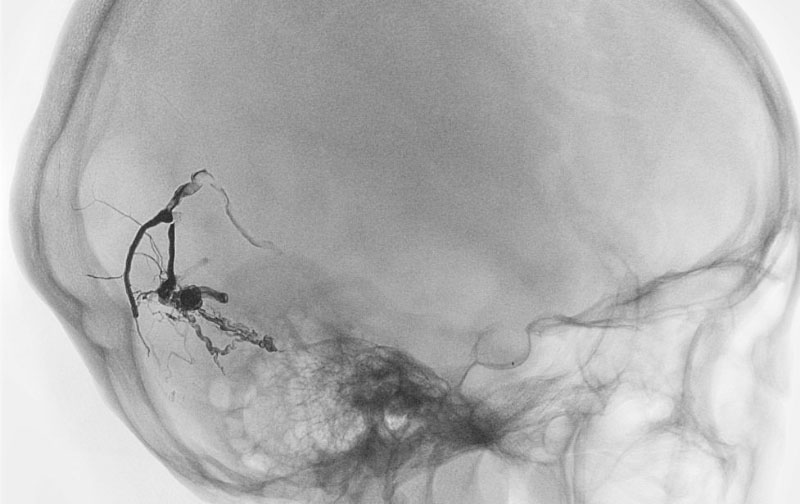

1586

'25年10月6日

硬膜動静脈瘻

40代

大阪府の病院

中

治療